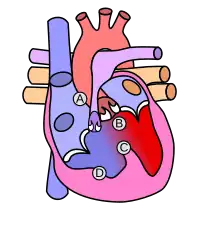

Heart with tetralogy of fallot A: Pulmonary stenosis; B: Overriding aorta; C: Ventricular septal defect (VSD); D: Right ventricular hypertrophy

Normal heart

Condition Description

Pulmonary Infundibular Stenosis A narrowing of the right ventricular outflow tract. It can occur at the pulmonary valve (valvular stenosis) or just below the pulmonary valve (infundibular stenosis). Infundibular pulmonic stenosis is mostly caused by overgrowth of the heart muscle wall (hypertrophy of the septoparietal trabeculae),[29] however the events leading to the formation of the overriding aorta are also believed to be a cause. The pulmonic stenosis is the major cause of the malformations, with the other associated malformations acting as compensatory mechanisms to the pulmonic stenosis.[30] The degree of stenosis varies between individuals with TOF, and is the primary determinant of symptoms and severity. This malformation is infrequently described as sub-pulmonary stenosis or subpulmonary obstruction.[31]

Overriding aorta An aortic valve with biventricular connection, that is, it is situated above the ventricular septal defect and connected to both the right and the left ventricle. The degree to which the aorta is attached to the right ventricle is referred to as its degree of "override." The aortic root can be displaced toward the front (anteriorly) or directly above the septal defect, but it is always abnormally located to the right of the root of the pulmonary artery. The degree of override is extremely variable, with 5-95% of the valve being connected to the right ventricle.[29]

Ventricular septal defect (VSD) A hole between the two bottom chambers (ventricles) of the heart. The defect is centered around the most superior aspect of the ventricular septum (the outlet septum), and in the majority of cases is single and large. In some cases, thickening of the septum (septal hypertrophy) can narrow the margins of the defect.[29]

Right ventricular hypertrophy The right ventricle is more muscular than normal, causing a characteristic boot-shaped (coeur-en-sabot) appearance as seen by chest X-ray. Due to the misarrangement of the external ventricular septum, the right ventricular wall increases in size to deal with the increased obstruction to the right outflow tract. This feature is now generally agreed to be a secondary anomaly, as the level of hypertrophy tends to increase with age.[32]